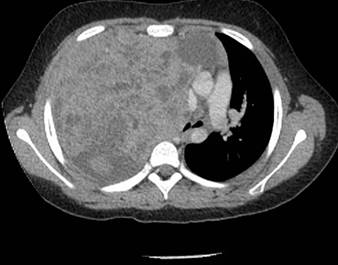

Dada la clínica se decide realizar radiografía de tórax (Figura 1) en la que se identifica derrame pleural derecho y una masa en segmento anterior del lóbulo superior derecho (LSD) con una lesión lítica expansiva en el segundo arco costal anterior derecho. Se amplia estudio con ecografía en la que se visualiza una masa pleural / pulmonar en segmento anterior de LSD con probable afectación mediastínica, derrame pleural derecho y alteración en la cortical del segundo arco costal anterior derecho. Se decide realizar TC torácico con contraste (Figura 2), (Figura 3) y (Figura 4) para valorar extensión y características de la lesión, identificándose una masa de aproximadamente 120x130x100 mm que ocupa casi todo el hemitórax derecho, heterogénea, con múltiples áreas quístico-necróticas en su interior. Condiciona desviación contralateral del mediastino y su infiltración, comprimiendo la vena cava inferior, sin claro plano de separación y contactando con el pericardio con signos de infiltración de la aurícula derecha. Comprime el bronquio principal derecho y sus ramas, condicionando atelectasia parcial secundaria y contacta con el segmento extrapericárdico de la arteria pulmonar derecha y ambas venas pulmonares derechas.

Figura 3: Se visualiza aumento de tamaño de la aurícula izquierda y derrame pleural derecho asociado. Parénquima pulmonar con un nódulo milimétrico en LSD.